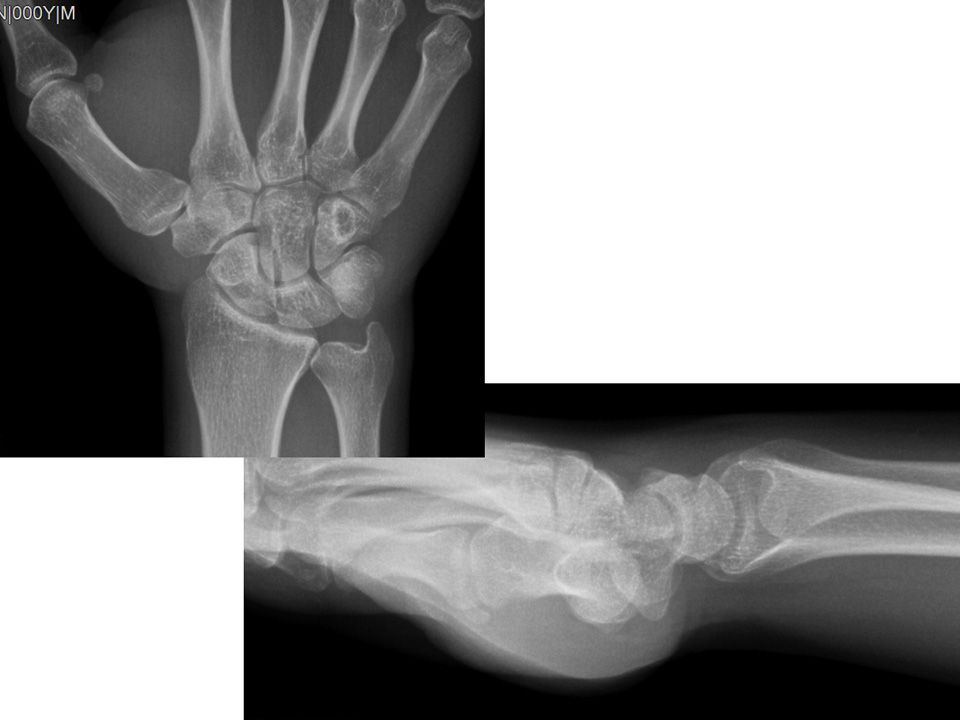

Case 05 - TFCC Injury 30 yr, male, quality control specialist, right hand dominancyFell on his right hand 2 months agoPain at dorsoulnar sideFovea sign +Pain on ECU tendon